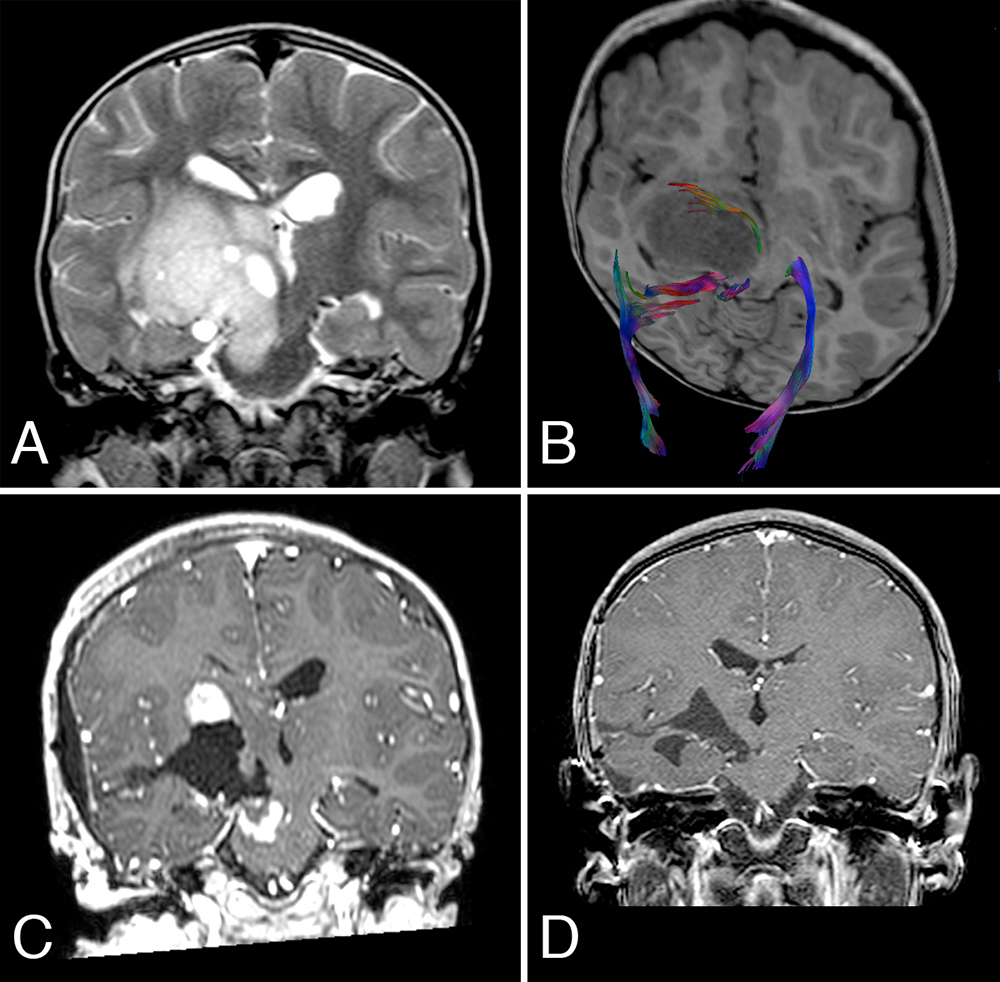

一般是进行核磁共振扫描。磁共振成像提供肿瘤的范围、生长特征以及瘤种和分级。另外,组织学诊断被认为是重要的评估和治疗方式,术前DTT通过丘脑周围白纤维束的可视化,使外科医生获得更顺利的手术入路。微创手段,例如激光治疗、立体定向针或内窥镜技术 [2],提高了手术精度,减少了对健康脑组织的医源性损害[3]。

较大限度地切除肿瘤而不增加术后缺损是手术治疗的目标。目前的丘脑胶质瘤外科治疗技术正逐渐演变成一种基于解剖学和瘤种考虑的定向治疗[4]。显微外科是较重要的治疗手段。影像学使肿瘤切除更顺利,成像技术允许更好的术前可视化和手术方法的选择,帮助定位病区[5]。